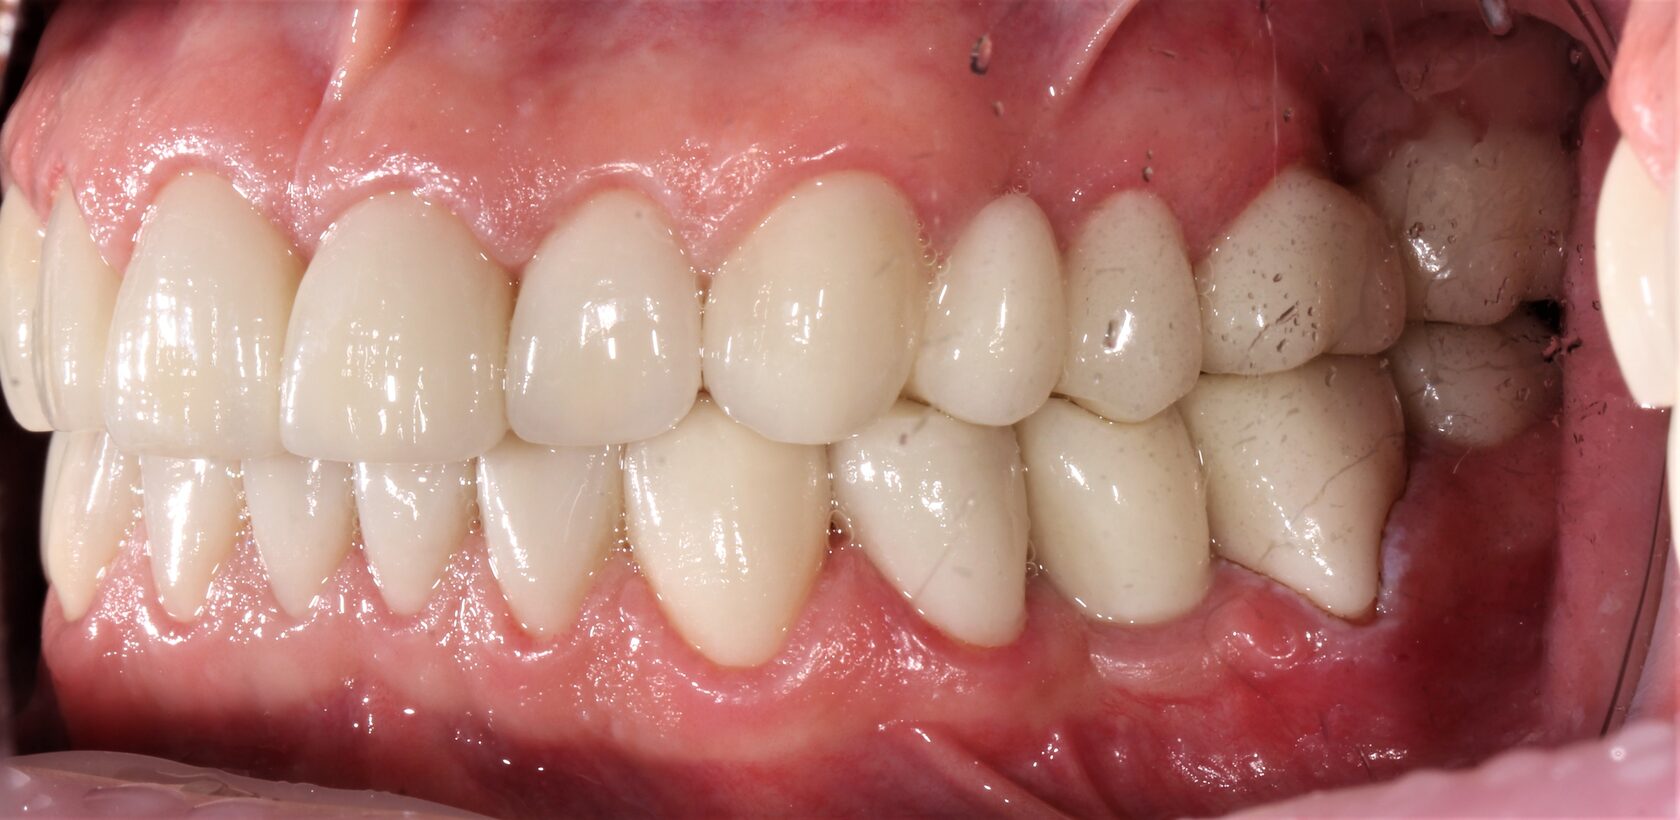

В данном клиническом случае представлена комплексная работа, состоящая из:

1 Терапевтический этап - лечение кариеса, подготовка корневых каналов и восстановление

культей зубов для установки коронок.

2 Хирургчий этап - удаление 2-х зубов с одномоментной дентальной имплантацией.

3 Сложное функционально-эстетическое протезирование (завышение прикуса на временных

коронках, стабилизация мышечного тонуса и позиции ВНЧС, перевод временных конструкций

в постоянные).

Длительность лечения составила более 1 год.